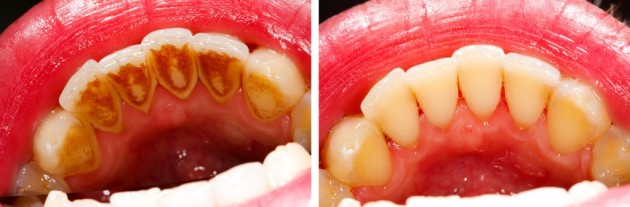

Ha ugyanis a baktériumok és az ételmaradékok nyállal keverednek a fogak felszínén, akkor kialakul a borzasztóan kemény fogkő; rosszul záródó tömések, koronák, torlódott fogak mind elősegítik a fogkő létrejöttét, amit otthoni eszközökkel már nem is tudunk eltávolítani. A fogkő eltüntetéséhez már fogorvos segítségét kell kérni, aki speciális eszközökkel szabadul meg a dentális plakknak nevezett szennyeződéstől.

A fogakon megjelenő fogkő esztétikailag sem egy szép látvány a barnás elszíneződés miatt, viszont még ennél is fontosabb, hogy a kezeletlen probléma fogínyvérzéshez és fogágygyulladáshoz vezethet, valamint a fogágy pusztulását és a fogak kilazulását okozhatja.